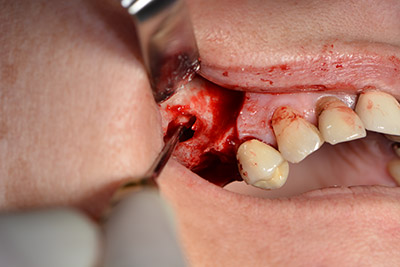

The next step was the sinus floor elevation with simultaneous implantation. The Implantmed also had a presetting at the first position for the buccal fenestration of the maxillary sinus wall.

The fenestration was prepared at 35,000 rpm and then the nasal mucosa were prepared in the cranial direction (Fig. 13 to 14).

The implant was then placed and the bone built up. In this case, because of the size of the augmentation region, autologous bone chips, harvested with an osseous trap as drilling chips from implantation 16 and fenestration 14, were mixed with bone replacement material.

An absorbable membrane was used as the barrier in the buccal direction and covered the augmentation. Finally, saliva-proof sutures were placed (Fig. 15 to 19).